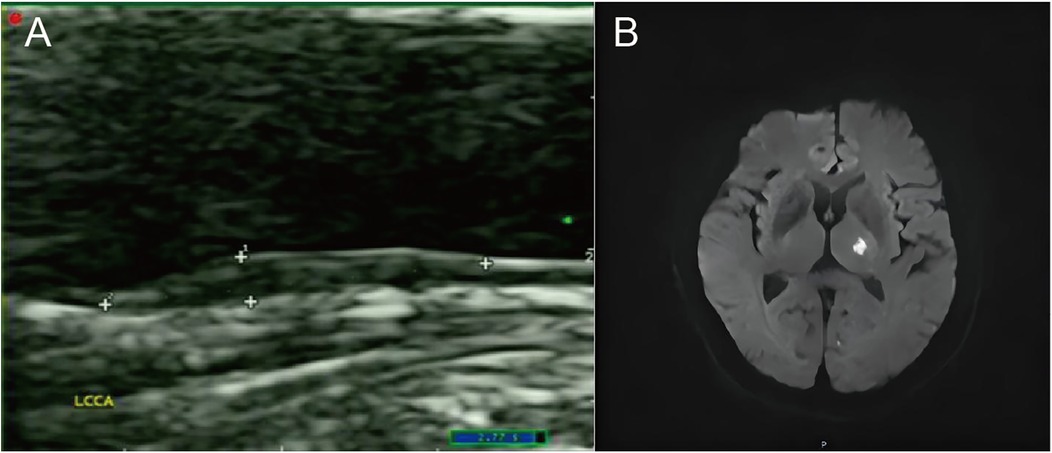

Table 2 lists the carotid-related measurements and US characteristics of plaques in ACIS and non-ACIS groups. Results revealed that among US characteristics of solitary Plaque-RADS-2 carotid plaques, only mainly hypoechoic characteristic was associated with ACIS (P < 0.05) (Figure 2).

Figure 2. A case of an ACIS patient with a solitary Plaque-RADS-2 carotid plaque. (A) The sonogram shows a mainly hypoechoic plaque on the posterior wall of the left common carotid artery. (B) Diffusion-weighted imaging (DWI) sequence shows high signal in the left basal ganglia.